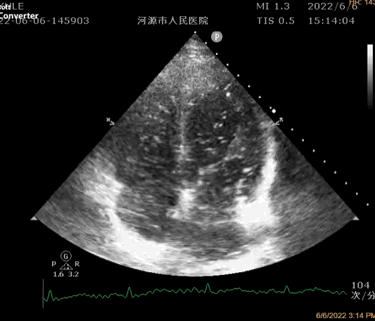

对比增强经胸超声心动图提示存在肺血管扩张

对比增强经胸超声心动图诊断肺内血管扩张的金标准,为无创检查。此方法是用振荡的生理盐水或靛青绿染料所产生的小泡(直径>20μm)静脉注入,当其从右心到达肺部时,因肺脏毛细管直径在8-15μm 之间,正常情况下并不能穿过肺泡的毛细血管。因此,不能在左心房内发现小泡的存在,若小泡离开右房/室经过3-6个心动周期后,可以在左房/室内发现小泡的回声则证实存在肺血管扩张。若小泡进入心房后迅速出现于左心,则提示有房室间隔缺损存在。